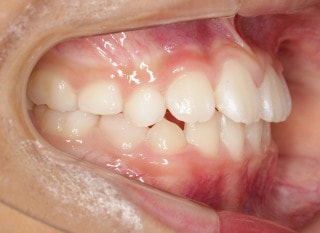

小児期第二段階

開始時

小児期の第二段階

治療中